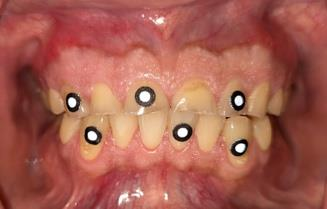

An intraoral assessment revealed moderate-to-severe tooth wear and an unaesthetic concave incisal plane. The periodontal tissues were healthy.

Beyond its esthetic contribution, the METISMILE® system offers a significant functional innovation. Using fluorescent markers on the maxillary and mandibular teeth, it records mandibular dynamics and converts the digital twin into a dynamic avatar, which is functionally equivalent to a digital axiograph. This enables the virtual articulator to be programmed individually for each patient.